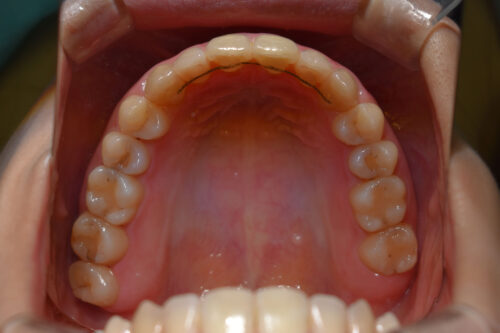

初診時年齢28歳女性

歯のがたつき(叢生)と

出っ歯

と

開咬

を気になさり

巣鴨 ・ 池袋よりひとつ隣駅の東京都豊島区大塚駅すぐの大塚たまみ矯正歯科へ

来院されました。

本症例も

矯正治療の精密検査後

非抜歯矯正治療計画を立案しました。

ワイヤー矯正治療9か月後です。